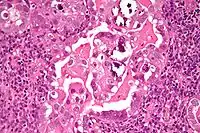

| Histology H&E of uterine serous papillary carcinoma. H&E stain. | |

Histopathologically, uterine serous carcinomas is typically characterized by (1) nipple-shaped structures (papillae) with fibrovascular cores (2) marked nuclear atypia (irregularities in the nuclear membrane, enlarged nuclear size), (3) psammoma bodies and (4) cilia.